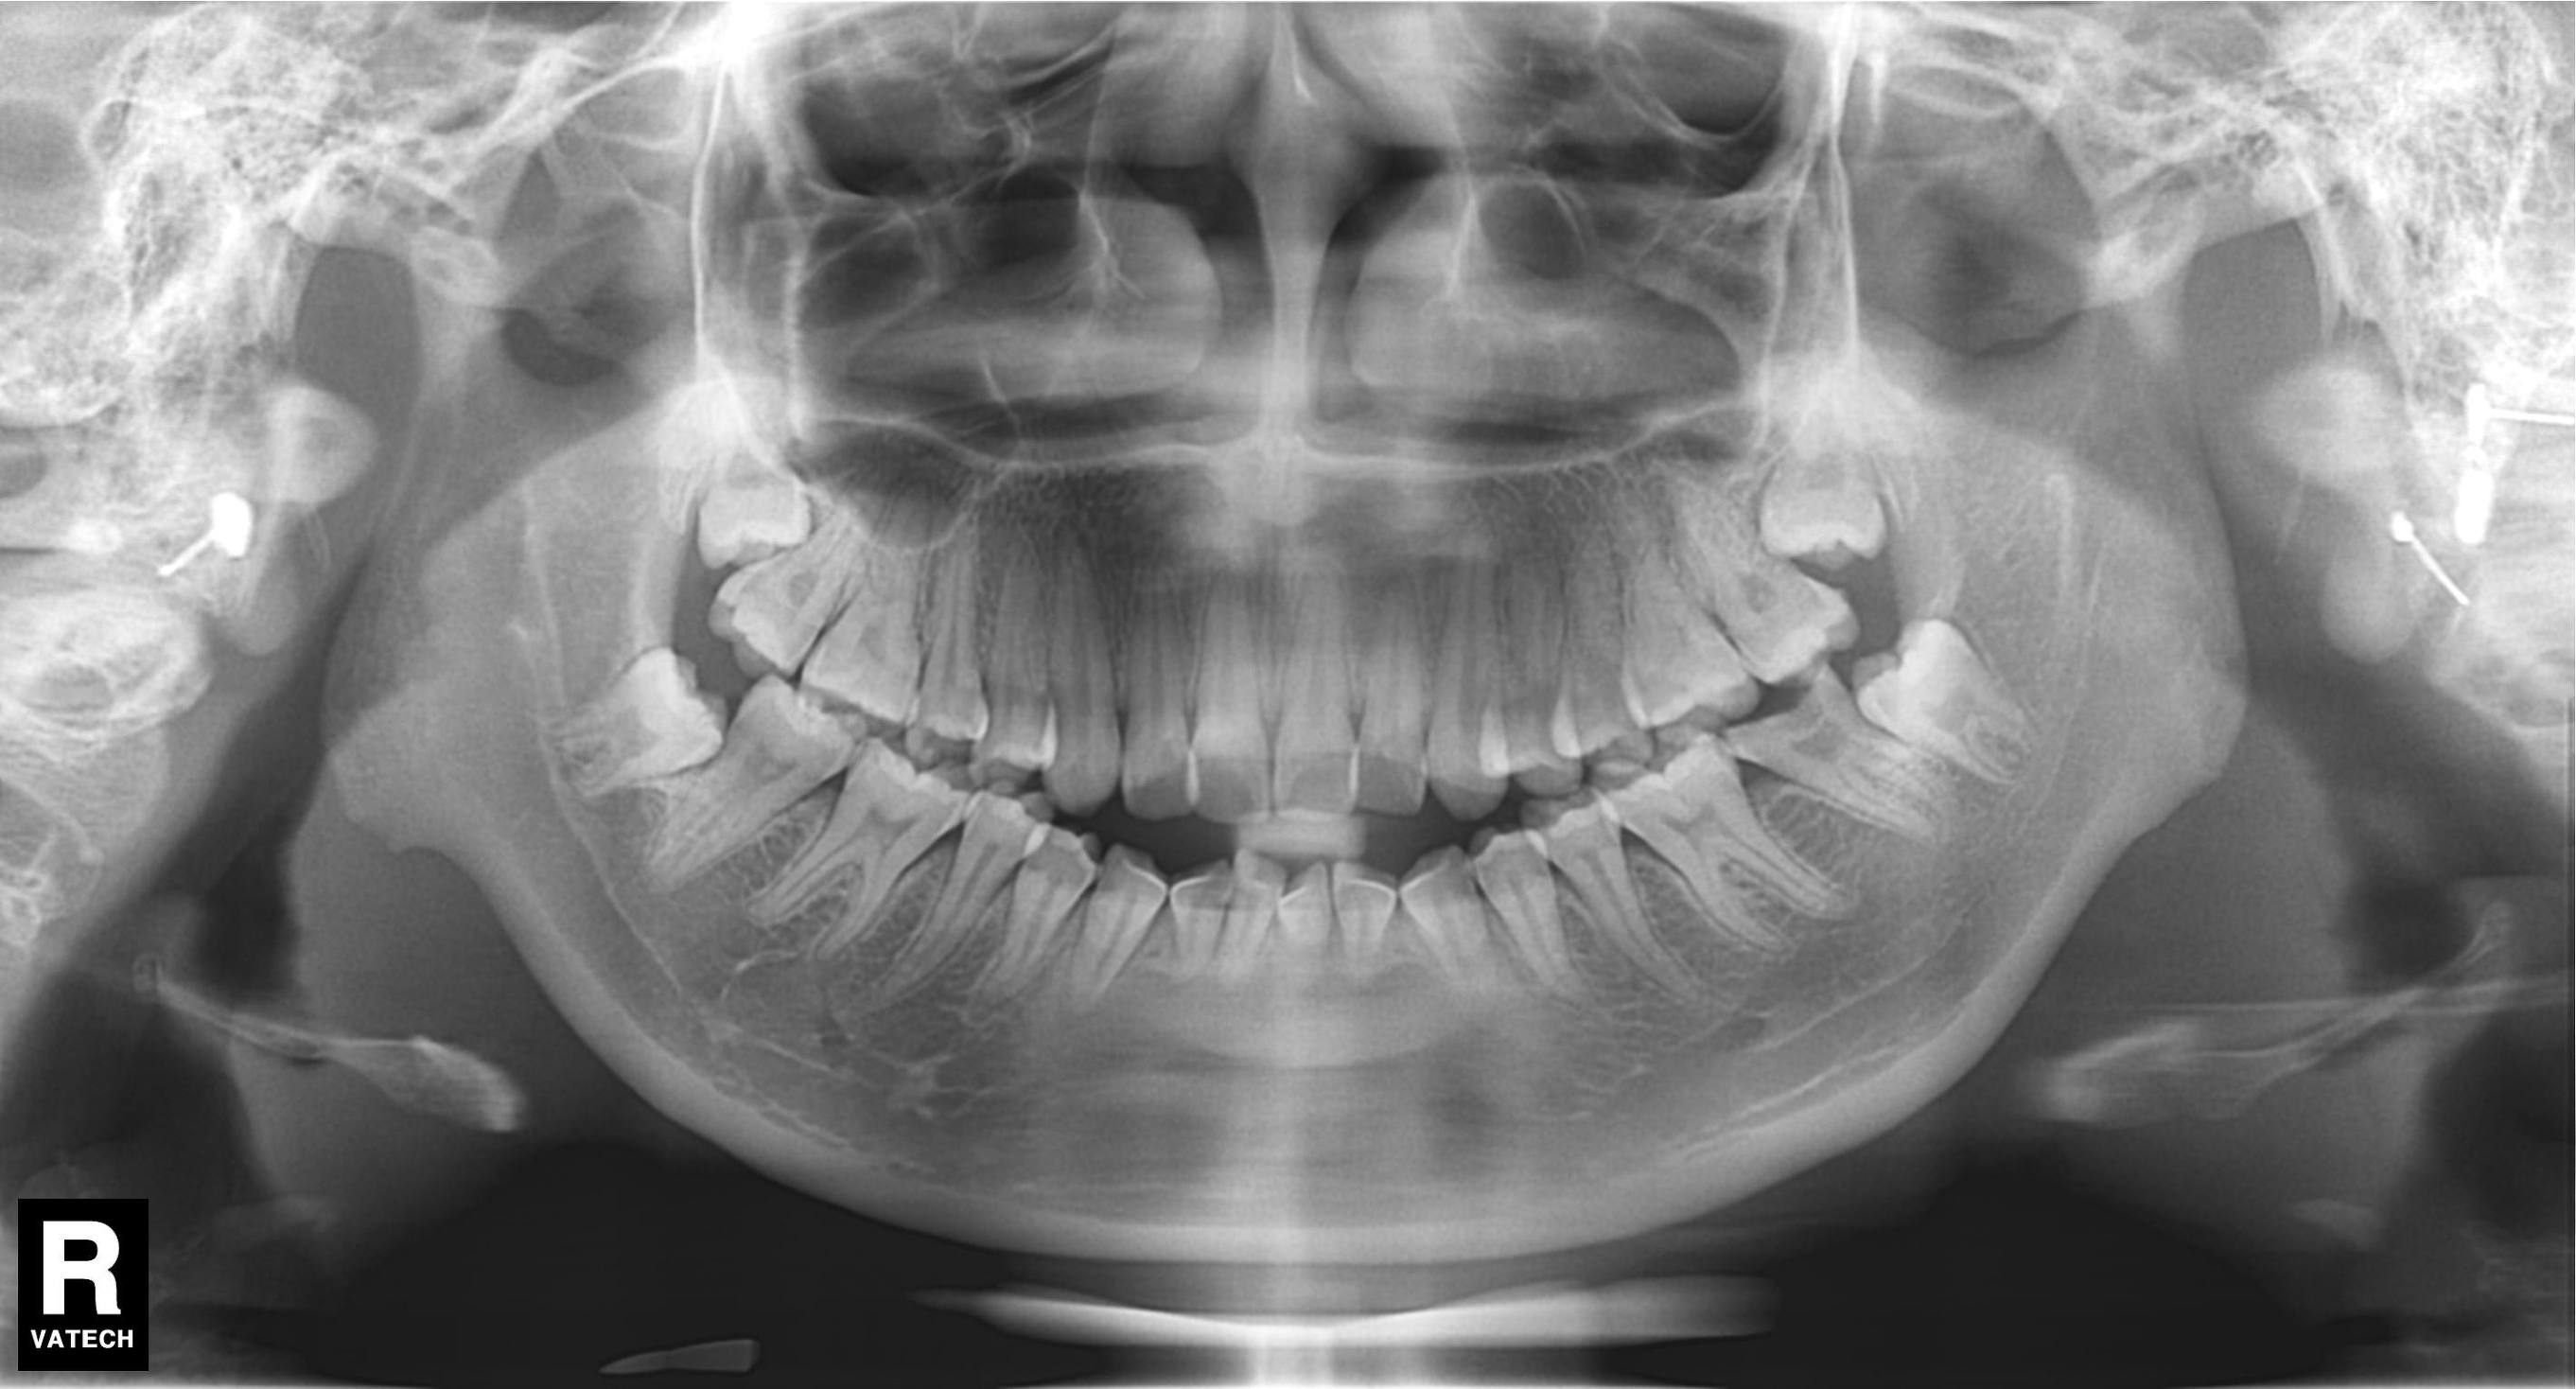

所以,当你去拍片后发现智齿是这样斜靠着的。

或者是这种躺在牙槽骨内的。